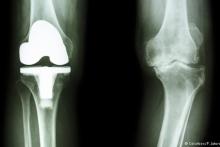

عمل جراحی تنها زمانی توصیه می‌شود که هیچ یک از روش‌های محتاطانه موثر نباشد. پیوند غضروف، پروتز و آرتروسکوپی از روش‌های موجود برای درمان به‌وسیله اعمال جراحی است. تشخیص بهترین روش درمان فقط در صلاحیت پزشک متخصص است.